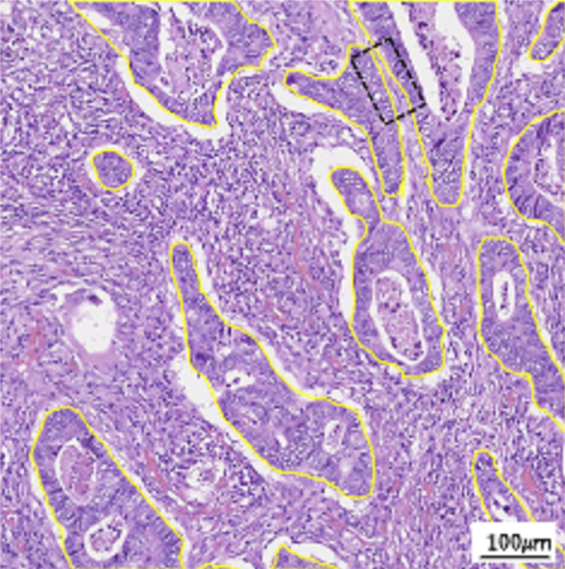

In the last few decades, the advent of computational pathology has catalyzed the advancements in clinical diagnosis, expedited development of new interactive models for pathology education and paved way for incredible rise in whole slide image analysis tools. It has revolutionized the entire tissue specimen analysis process for pathologists. From manually analyzing thousands of tissue slides via microscope requiring specialized doctors to automatic digital slide generation via scanning and using AI based deep learning techniques has spawned fatal disease diagnosis such as cancer using image analysis. In digital pathology nuclei and gland instance segmentation in whole slide images is of pivotal value for abnormality assessment. It plays a key role in histopathological image analyses whether it be identification of major chronic disease including tumor localization through segmentation or classification as benign or malignant. Glands are often considered as one of the main histological structures present in most of the organs as primary mechanism for proteins and carbohydrates secretion. However, it has been observed that adenocarcinomas, regarded as the most severe type of cancer, originates from glandular epithelium as malignant tumors. In figure 1, left patch shows histopathological image of a colon tissue stained with routinely used Haematoxylin and Eosin technique while right patch is individual gland of a colon tissue with sub structures. This makes understanding of glands morphology a pivotal step for assigning degree of malignancy of major adenocarcinomas e.g in breast, colon, lung and prostate. Thus accurate gland instance segmentation is considered as a necessary step for obtaining valid morphology information.

Gland Segmentation Challenge dataset (GlaS) is first used as part of MICCAI-2015. This data is extracted from 16 Haematoxylin and Eosin H&E stained Whole slide images (WSIs) scanned through MIRAX MIDI Slide Scanner pixel resolution at 20 x magnification. It consists of total 165 images out of which 85 are used as training (48 malignant and 37 benign) and 80 test images including (43 malignant and 37 benign). Size of images is 775 x 522 pixels each having associated instance-segmented ground truths highlighting glands boundaries align with accurate lumen annotations for glands.

3.2.2 CRAG

CRAG (Colorectal Adenocarcinoma Glands) dataset is primarily comprised of gland images. It consists of colon adenocarcinomas usually referred as colorectal gland (CRAG) dataset developed by University Hospital Coventry and Warwickshire (UHCW) NHS Trust Coventry UK. It composed of 213 H&E stained CRA images from 38 whole slide images (WSIs) scanned by VL120 scanner at 20 x objective magnification and are mostly of size 1512 x 1512 px along with instance level ground truth. Training and testing images are 173 and 40 specifically with varying cancer grades.